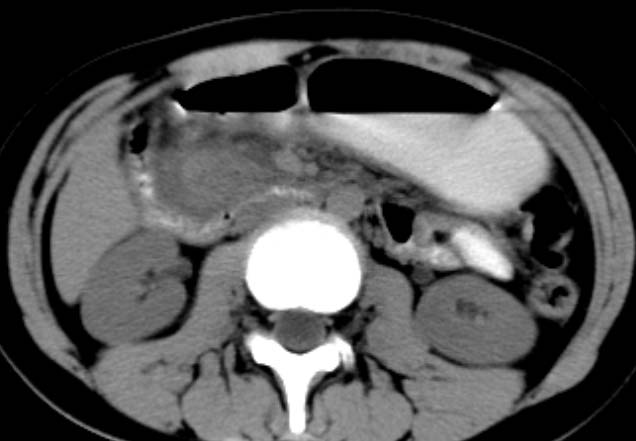

女,14岁。腹痛3天。腹部触诊未触及包块。碘剂阳性未增强。求助战友。。。。。。。。。。。

胰头部明显肿大,胰周间隙浸润,考虑胰腺炎可能性大

胰头部增大,周围模糊,有渗出,胰腺炎可能性大,建议结合化验检查;左侧输尿管上段略扩张.

胰头部明显肿大,胰头周脂肪密度加大。十二指肠环扩大受压。胰管未见确切扩张。考虑胰腺炎可能性大。建议增强扫描。

胰头部增大,周围结构模糊,并明显见渗出。支持:急性胰腺炎!

1)急性胰腺炎。2)肝右叶后上段肝内胆管结石。3)左侧输尿管上段扩张,原因待查。

胰头明显增大,周围结构不清,诊断胰腺炎的话,结合血或尿淀粉酶诊断比较明确了。

胰头部明显增大,胰管未见明显扩张,周围肠系膜血管显示清楚,胰头周围明显见渗出,还是考虑胰腺炎

胰头明显肿大呈肿物样,周围脂肪密度增高,结合病人年龄及临床表现,首先考虑炎性改变,建议结合实验室检查明确。必要是复查或mr检查

病灶应在胰头下区,不一定是胰头,结合周边低密度水肿,是否可能为十二指肠(xi)室炎症或其它炎症。

胰周无明显渗出,吉氏筋膜未见增厚。血尿试验室检查不支持。排除胰腺炎。